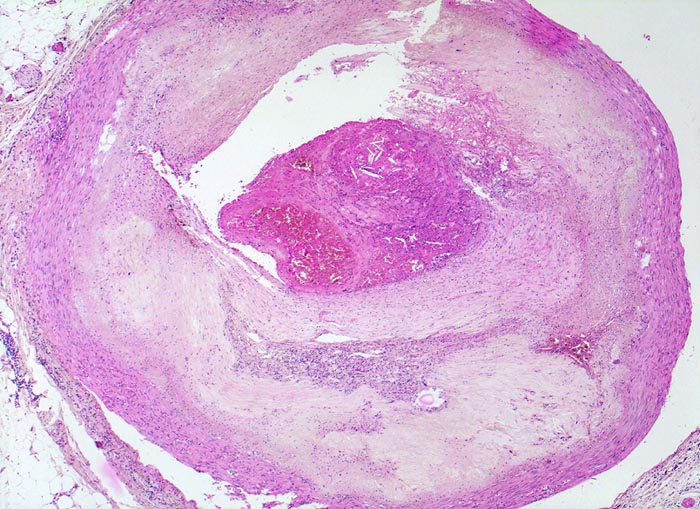

Koronarsklerose mit Thrombose

Konzentrische Atherosklerose der Koronararterie. Massive Sklerose und Verbreiterung der Intima. Neovaskularisationen in der Intima. Atrophie der Media. Partiell organisierte Thrombose über einem rupturierten Atheromherd. Der Thrombus enthält Cholesterinkristalle aus dem rupturierten Atherom.

Subakuter transmuraler Myokardinfarkt. In der Anamnese Nikotinabusus und schlecht eingestellte arterielle Hypertonie.

Myokardinfarkte treten oft als Folge eines thrombotischen Verschlusses nach Plaqueruptur eines nur mässig stenosierten Gefässes auf (angiographisch 35-65% Stenose). Kleine lipidreiche Atherome rupturieren häufiger als stark fibrosierte Plaques mit schwerer Stenose. Schwere Stenosen führen trotz Tendenz zum thrombotischen Verschluss seltener zu einem Infarkt wegen gut ausgebildeter Kollateralkreisläufe.